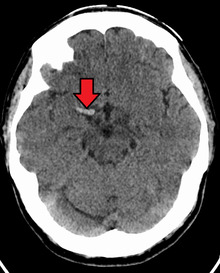

Cerebral venous sinus thrombosis (CVST) is a rare form of stroke which results from the blockage of the dural venous sinuses by a thrombus. Symptoms may include headache, abnormal vision, any of the symptoms of stroke such as weakness of the face and limbs on one side of the body and seizures. The diagnosis is usually made with a CT or MRI scan. The majority of persons affected make a full recovery. The mortality rate is 4.3%.[4]